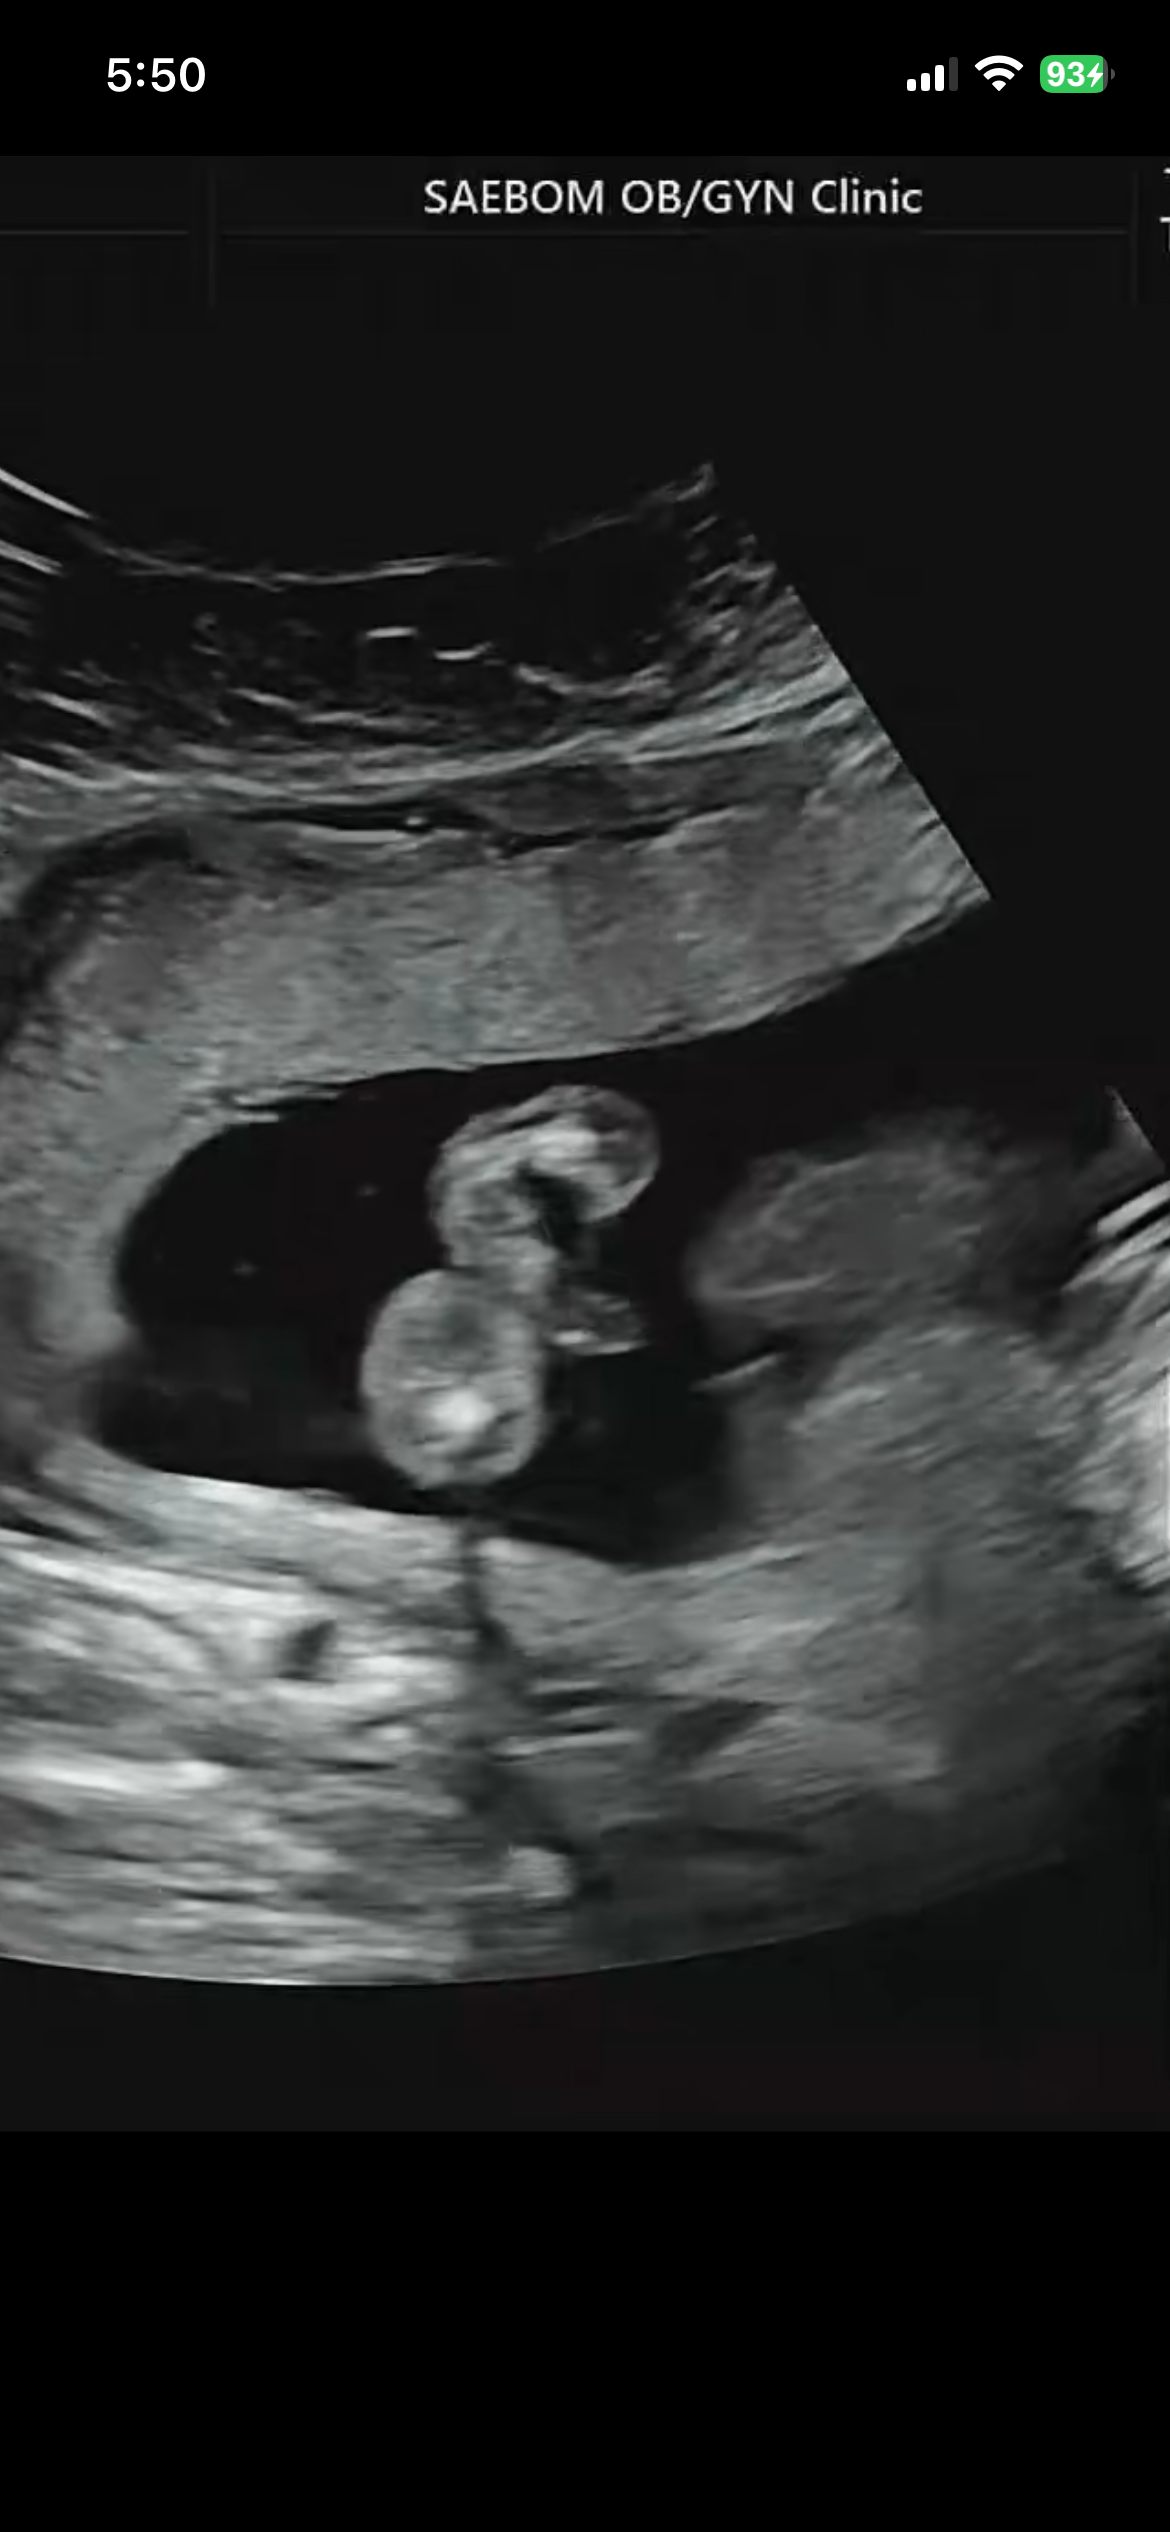

성별15주6일

아들 확정일까요? 반전은 절대없겠죠?